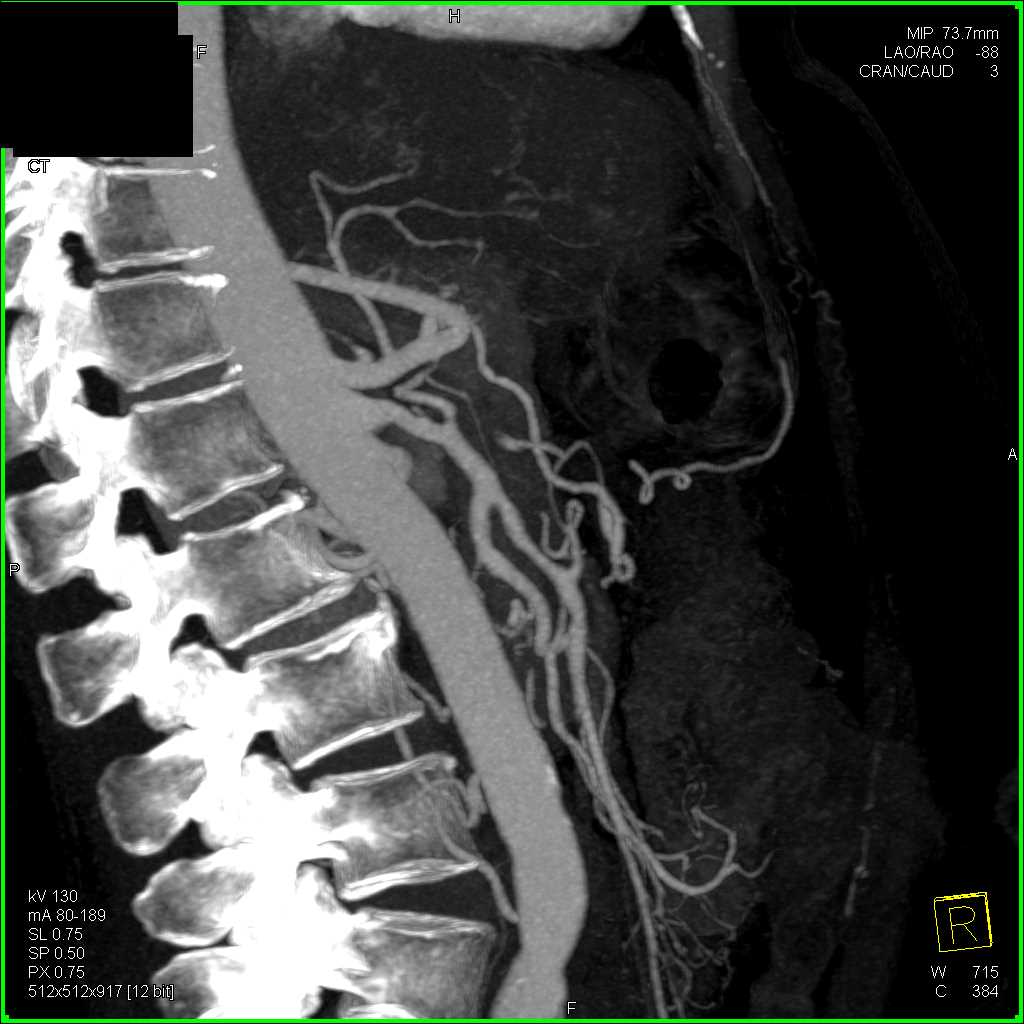

Neuroendocrine Tumor Body of Pancreas